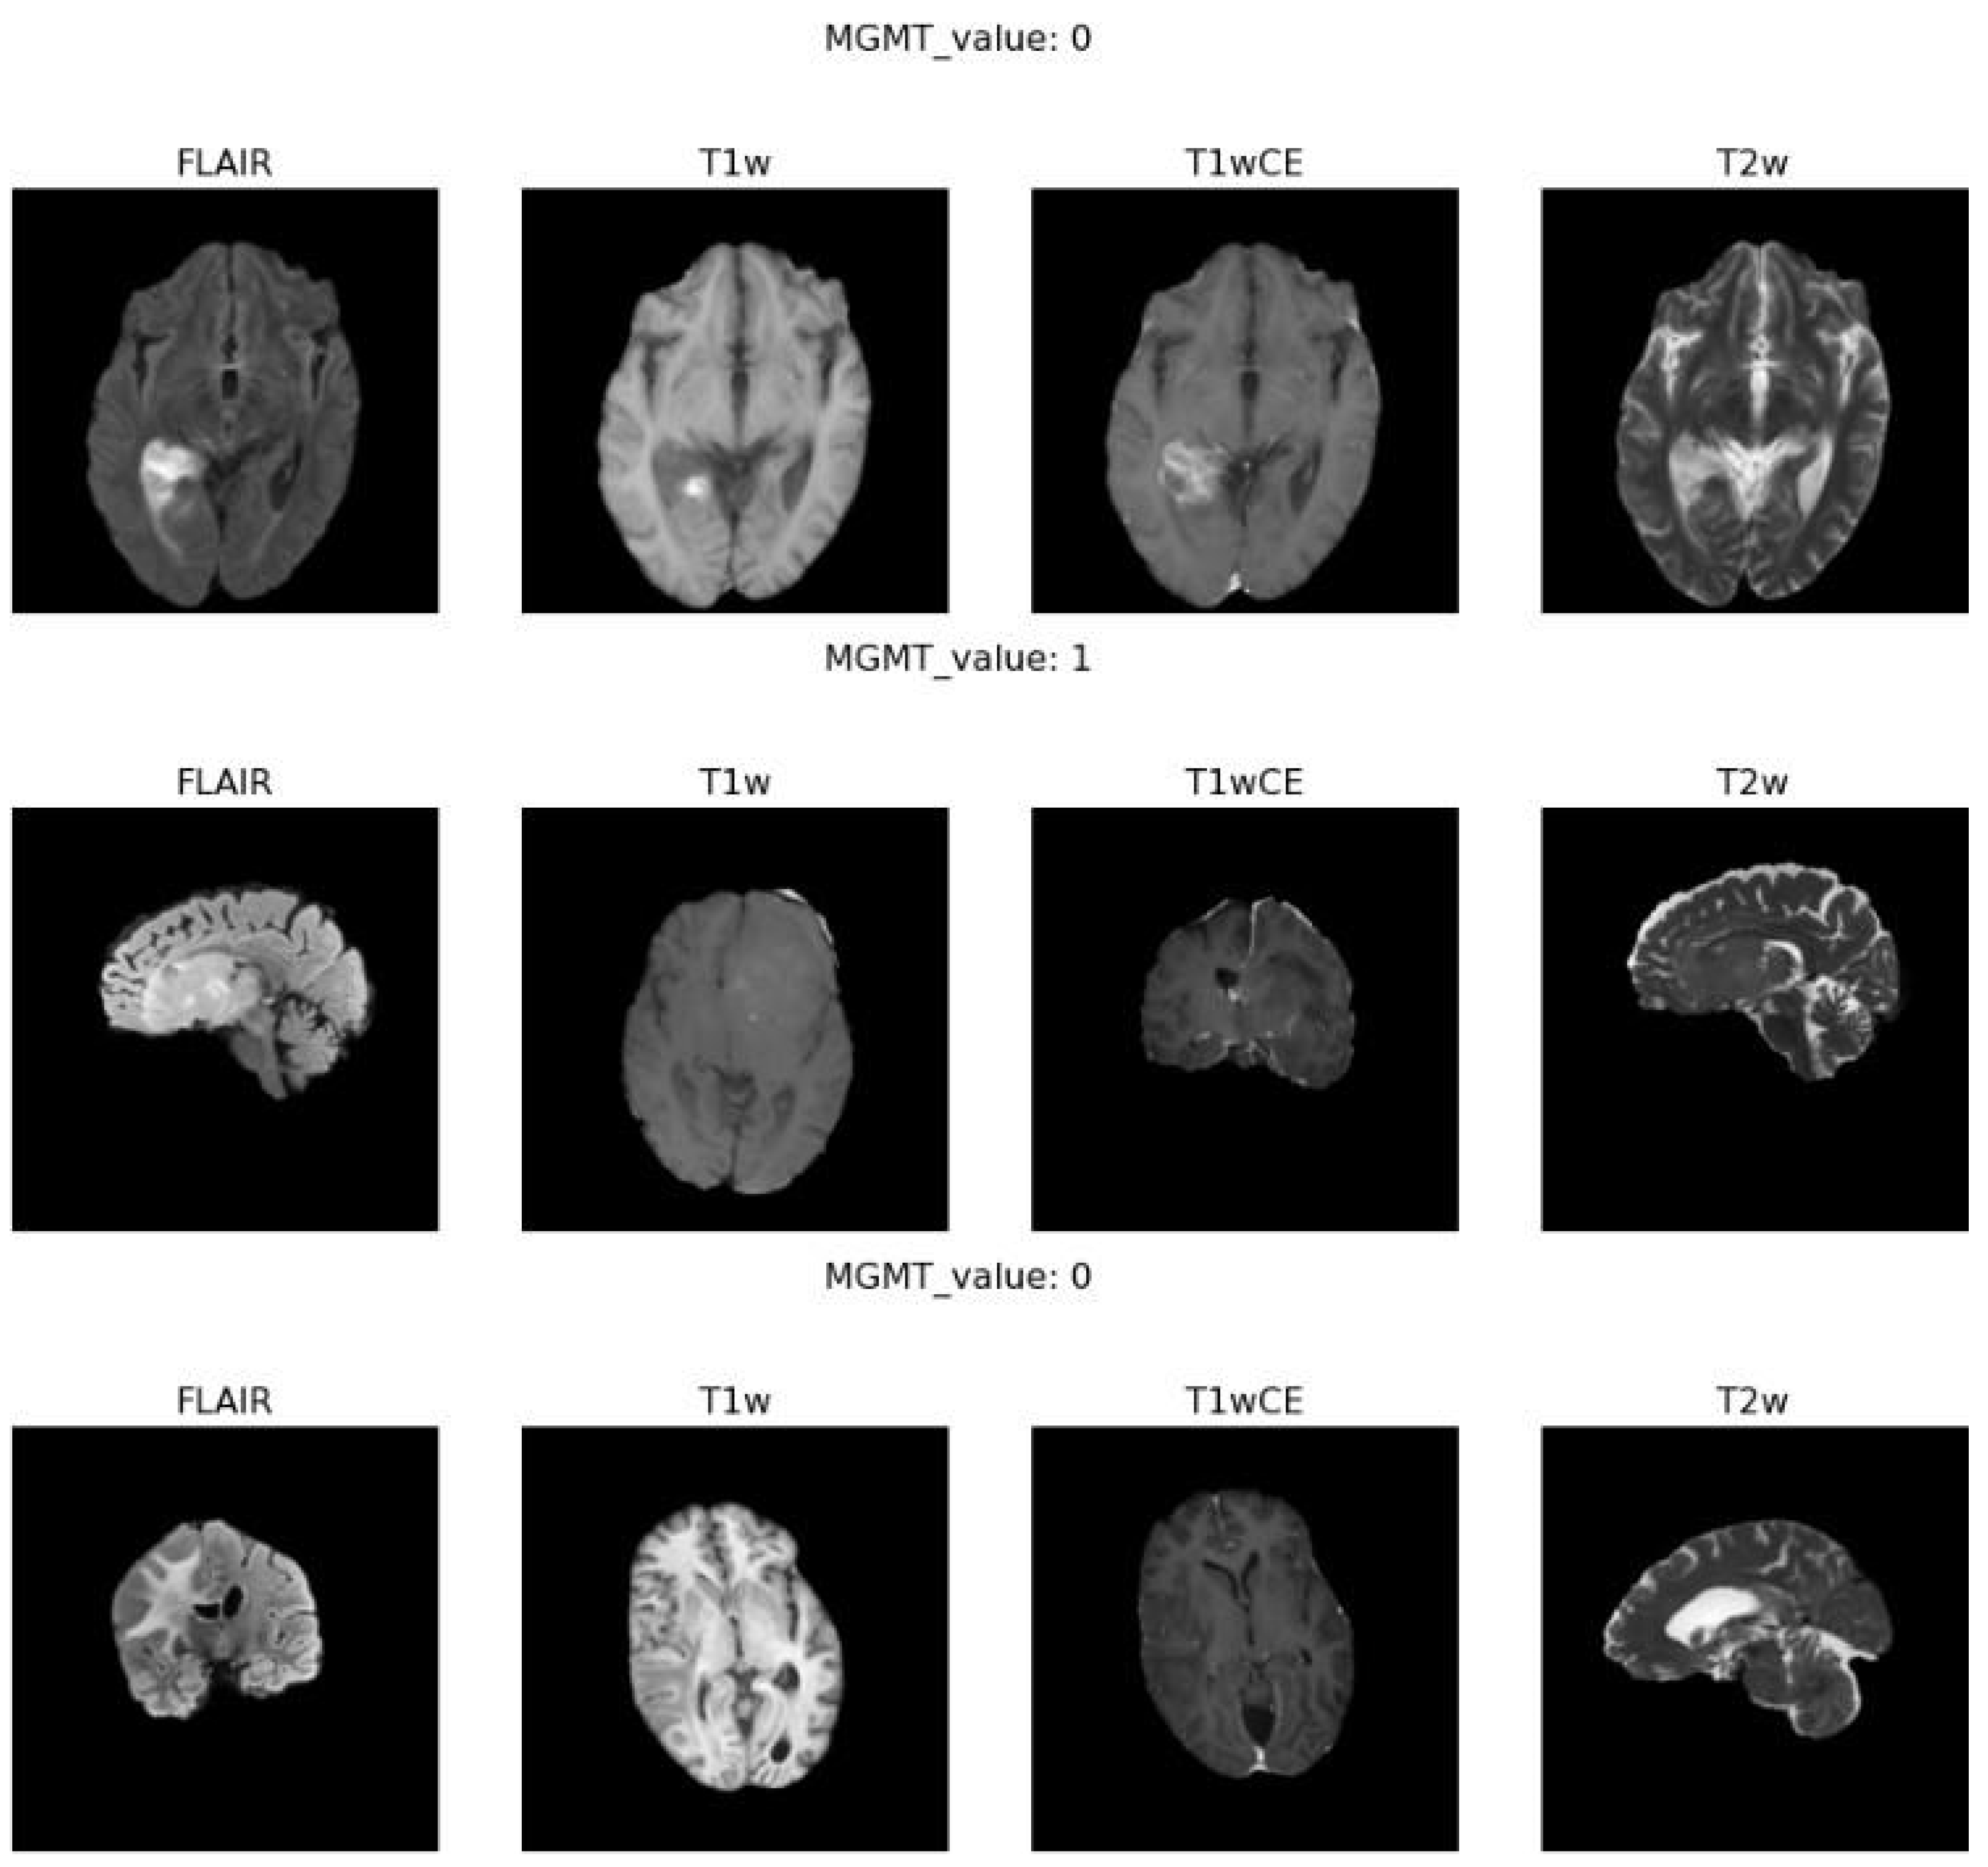

Sample MRI Visualization